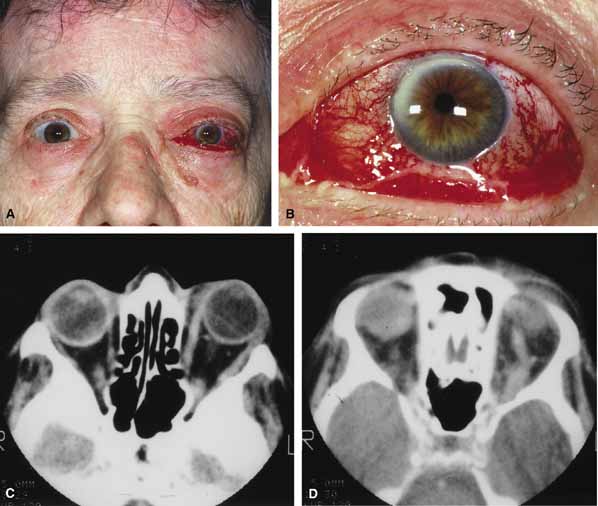

Although there have been a few reports of mucormycosis occurring in healthy individuals, virtually all other patients have had previous severe underlying disease. The patient most vulnerable to this infection is an one with uncontrolled diabetes with ketoacidosis. A host of other conditions also predispose patients to the disease including: multiple myeloma, lymphoma, organ transplantation with immunosuppresion, chemotherapy, corticosteroid treatment, acquired immunodeficiency syndrome, etc.(Fig. 2A).12–14 Mortality is extremely high for patients with phycomycosis infection, and successful treatment is contingent on early recognition and prompt treatment.

Fig. 2 A. A 65-year-old man with a myelodysplastic disorder and pancytopenia developed a pimple on the side of his nose followed by rapidly developing cellulitis and skin necrosis. The patient developed a frozen globe and loss of vision over a matter hours. Despite aggressive surgical debridement of the necrotic areas and intravenous, amphotericin, the patient died. B. Black eschar (necrosis) along right side of nose, ala, upper lip, and hard palate. C. Right orbital infiltration is seen along with opacification of the right ethmoid sinus and nasal passage. D. The optic nerve is on stretch with tethering of the globe, extensive soft tissue swelling anteriorly, ethmoidal opacification, and enlargement of the right medial rectus muscle.

Characteristic features of orbital mucormycosis include an immunocompromised patient with sinusitis, pharyngitis or nasal discharge who develops cellulitis of the face or lid. Signs and symptoms include orbital/periorbital pain, acute proptosis, abrupt visual loss, orbital apex syndrome with acute motility changes (external ophthalmoplegia), pupillary changes (internal ophthalmoplegia), ptosis, and decreased corneal sensation. Infarction of tissue results in black eschar formation of the skin, nasal mucosa and hard palate (Fig. 2A and 2B).12,13 With intracranial extension, the patient generally become obtunded, develops convulsions, contralateral hemianaesthesia or hemiplegia, and lapses into coma.

CT scanning demonstrates an orbital mass often with bone destruction and sinus involvement (Fig. 2C and 2D). The diagnosis is confirmed by biopsy of involved tissue with demonstration of characteristic nonseptate, large, branching hyphae, which can be seen on routine hematoxylin and eosin stains. Material should be submitted for both frozen and conventional paraffin-embedded sections. Frozen sections are not always definitive and the surgeon must have considerable confidence in the skill of the pathologist. 13 Management includes: (1) early definitive diagnosis; (2) correction of any underlying metabolic disturbance; (3) wide local excision with debridement of all involved and devitalized oral, nasal, sinus and orbital tissue; (4) establishment of adequate sinus and orbital drainage; (5) daily irrigation and packing of the involved orbital and paranasal areas with amphotericin B; and (6) intravenous amphotericin B.12,13,15